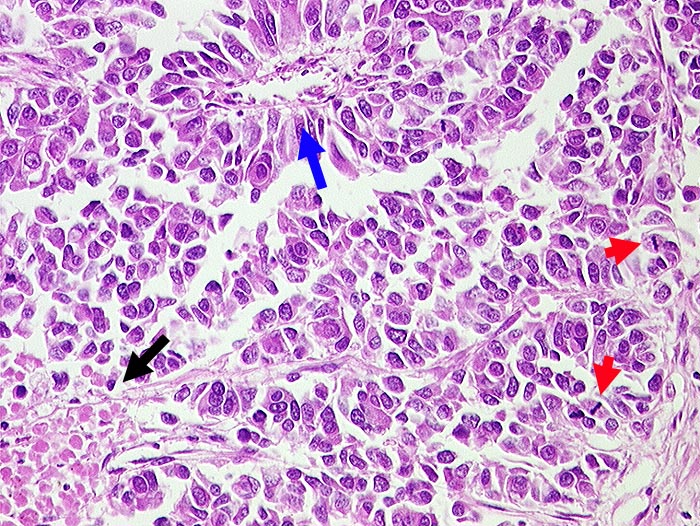

PathoPic ID 538 - Grosszelliges neuroendokrines Karzinom

Grosszelliges neuroendokrines Karzinom

maligner Tumor

Lunge

Mittelgrosse Tumorzellen mit reichlich Zytoplasma und zahlreichen Mitosen.

Herdförmige Nekrosen.

Pseudorosettenbildung um Gefäss.

Zentrales Bronchuskarzinom. Synaptophysin und NSE positiv.